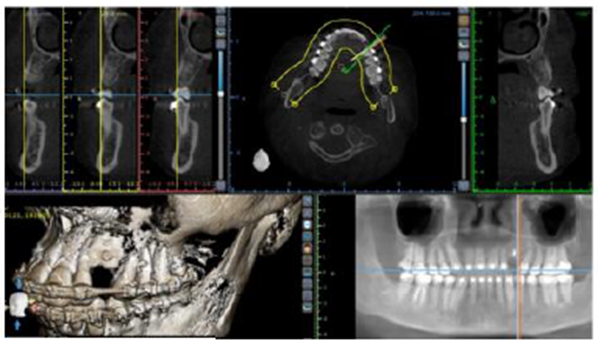

Paciente do sexo feminino, 30 anos, foi encaminhada para restauração com implante na região do canino superior esquerdo. Para obter uma avaliação precisa do volume ósseo tridimensional, foi realizada uma tomografia computadorizada Cone Beam que revelou uma deficiência óssea vertical (Figura 1).

Antes da instalação do implante, tornou-se necessário um aumento vertical cirúrgico para que o implante pudesse ser colocado em uma posição tridimensional correta (Figura 2).